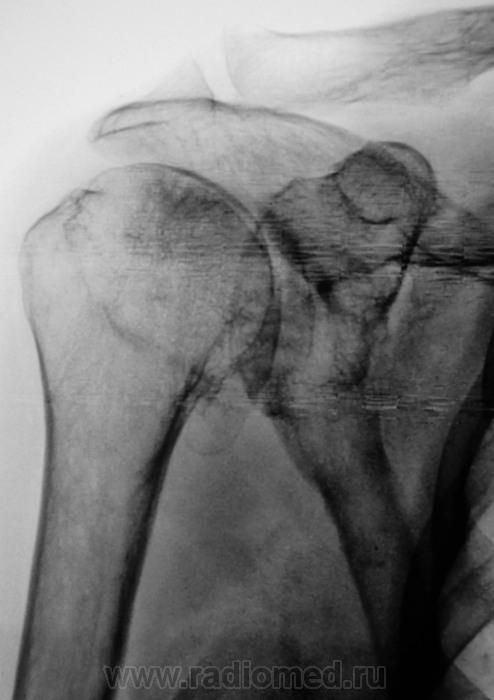

Жалобы на длительные боли в плечевом суставе

Таков артроз.

Смущает дополнительный "контур" по стрелкам.

Думаю,что это "неодокостеневшие" костные разрастания(не знаю,как точно обозвать).

ДОА.

Что в анамнезе? Была травма? После чего боли появились. Что можно сказать об объёме движений? Мне кажется, что изменения связаны с обызвествлением суставной сумки.

Мне кажется, что изменения связаны с обызвествлением суставной сумки.

Мне тоже так показалось.

Для оценки состояния хрящевой губы МРТ

А может быть для начала УЗИ? Пока она до МРТ доедет. Есть такое понятие "замороженное плечо". Возможно оно, вот узнать бы объём движений.

Вот, вот, пациентка так и говорит, что как бы плечо замерзло. Объём движений пациентной оценивается, как нормальный, но боли мешают...